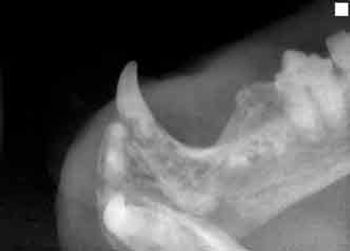

Q. How do you proceed when you have a cat anesthetized and find that a tooth (or teeth) you need to extract is fused to the mandible?